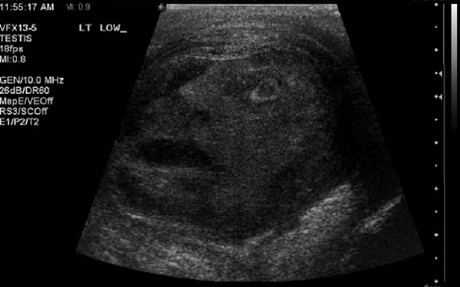

Um susto é o mínimo que terão sentido paciente e equipa do Hospital da Universidade de Queen, em Ontário, Canadá, ao darem com um rosto numa ecografia! Aconteceu com um homem de 45 anos que tinha uma massa estranha num testículo... Afinal, era ‘apenas’ um tumor benigno!